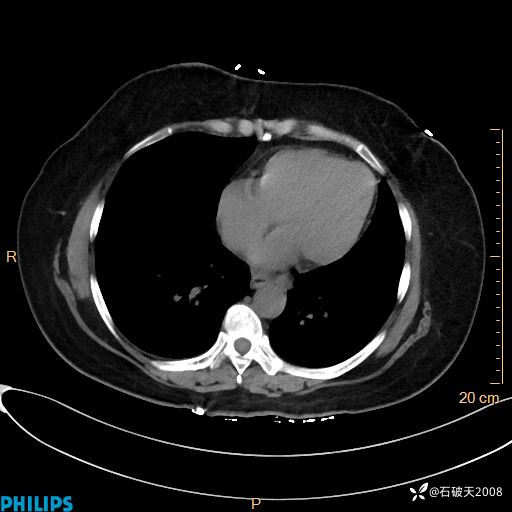

肺结节病?纵膈型肺癌?淋巴瘤?有点意思,欢迎围观

女 52岁 主 诉:咳嗽10余天,咳痰2天。

动脉期

静脉期